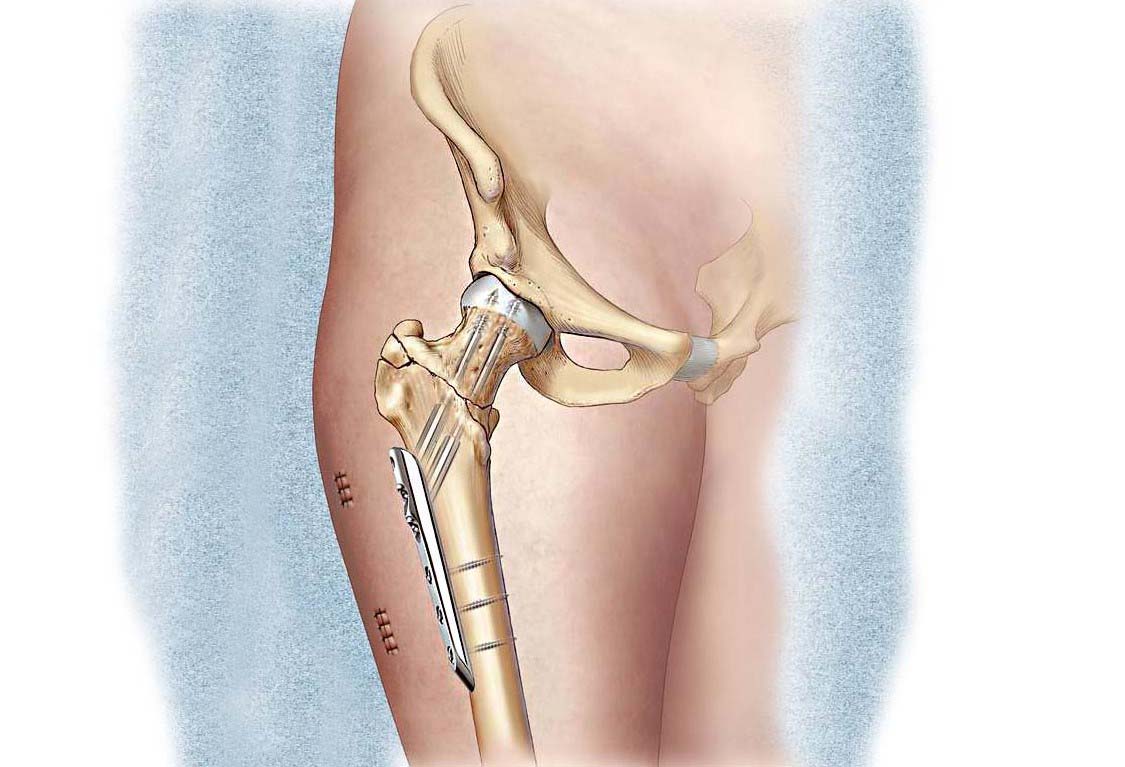

Оссификация тазобедренных суставов: что это и как проявляется?